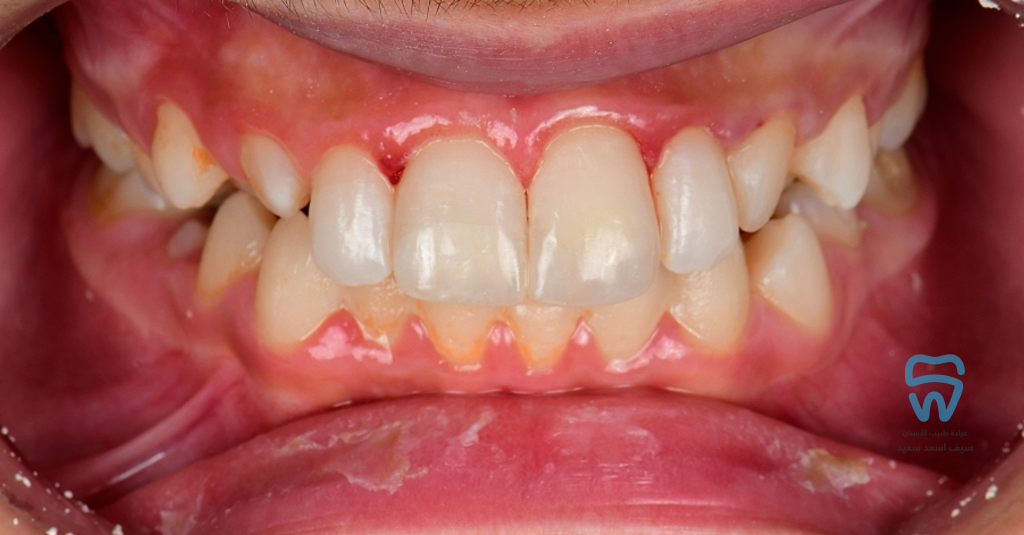

At the restoration's polishing visit the patient came back with another trauma on the left central within two days of the restoration

Finished and polished

1 year follow-up